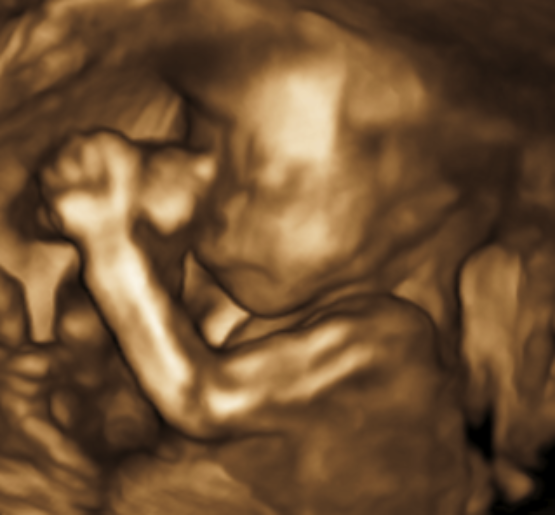

"Your baby's being lovely," Jackie reassures her. One of the benefits for the volunteers taking part in the project is that they get to take home a whole set of 2D and 3D images from the ultrasound, as well as some video material of the baby from the MRI scan later in the day. Jackie tries to get some good images of the baby's face for Rebecca.

The team takes multiple images of Rebecca's baby over the course of an hour, making sure to save some video footage to a disc for Rebecca to take home.

We head back up to Dr Lloyd's office. One of the early successes of the iFind project has been applying algorithms to MRI images that can account for a baby's movements. "That's how we managed to make this heart," says Dr Lloyd. "From an MRI scan that we were able to 'correct' to make a 3D model."